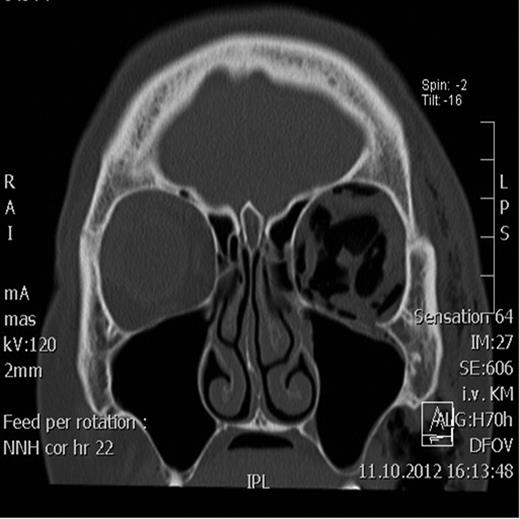

Spiral computed tomography (CT) was performed using 1 mm slices with a soft tissue and bone algorithm. A non-dislocated orbital floor fracture and a large amount of intraorbital emphysema were found, especially retrobulbar between the ocular muscles and around the optic nerve, causing exophthalmos (the distance from the corneal apex to the line connecting orbital rims was 18.8 mm; normal 9.0 mm) (Figs 1–2).

Coronal CT scan showing the retrobulbar emphysema prior to decompression.